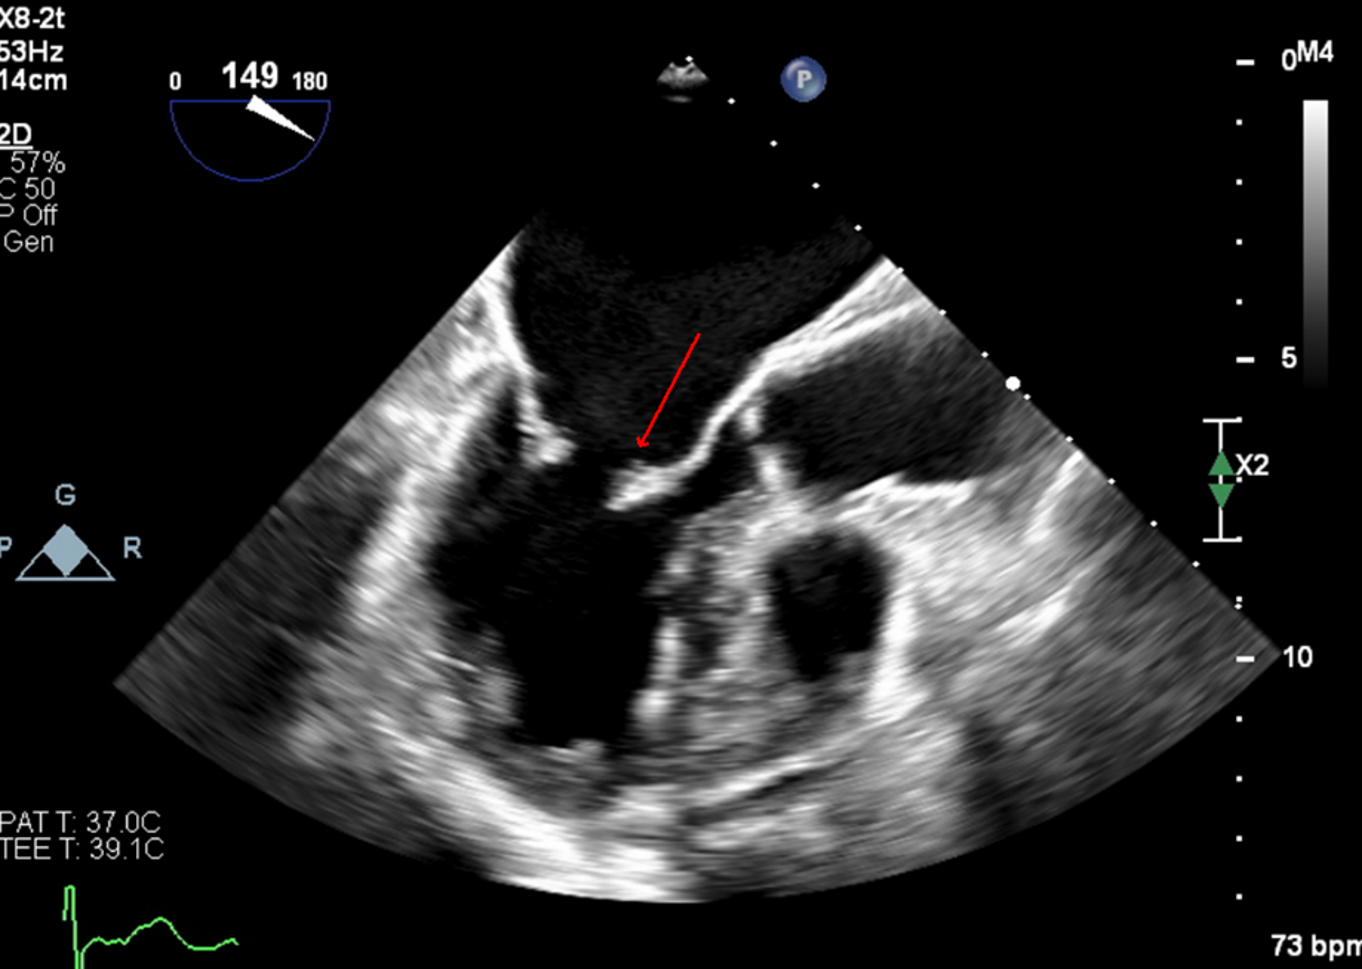

Case Presentation: A 67 year-old female presented to the ED with acute left upper extremity paresis and facial droop. She had 2 previous cardioembolic strokes, in 2007 from mitral nonbacterial thrombotic endocarditis for which she started warfarin and in 2010 after stopping warfarin for 8 months due to menorrhagia. Warfarin was switched to apixaban in 2021 due to patient preference. She also had atrial fibrillation (AF) with CHA2DS2-VASc 5 (diagnosed 2020), mild-moderate mitral regurgitation (on 2020 echocardiogram), hypertension, hyperlipidemia and a 37 pack-year smoking history.She was hypertensive (BP 172/89) with otherwise normal vital signs. Examination was significant for NIHSS 2 (left upper extremity drift and facial droop) and an irregularly irregular pulse. EKG confirmed AF. CT head and neck angiogram showed a proximal right M2 occlusion (Fig.1) with distal flow reconstitution and patent carotid arteries.Neurology, Vascular medicine and Cardiology teams were consulted. She was not a thrombolysis candidate due to apixaban intake and mild signs/symptoms. Apixaban peak and trough levels were both within the expected therapeutic range with anti-Xa levels of 130 and 77 respectively. Thrombophilia testing was negative for protein C, prothrombin gene mutation, factor V Leiden and antiphospholipid antibodies. Work-up for malignancy with CT imaging and cancer screening was unremarkable.Transesophageal echocardiogram was obtained to assess for a cardioembolic cause of stroke and revealed a hockey-stick appearance of the anterior mitral leaflet which is classic for rheumatic valve disease (Fig.2), moderate mitral stenosis and moderate mitral regurgitation. Ejection fraction was preserved at 50% and there was no intracardiac mass or patent foramen ovale.Apixaban had been inadequate anticoagulation as she now had both moderate rheumatic mitral stenosis and atrial fibrillation. She was bridged to warfarin with target INR 2-3 and discharged to valve clinic for follow-up.